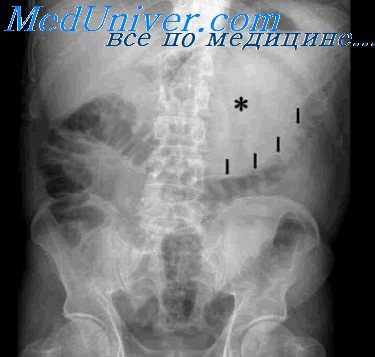

Диффузная железистая гиперплазия сопровождается резким увеличением калибра и количества складок, высота которых может достигать 2,5—3 см, а ширина 2 см. Массивные беспорядочно и тесно расположенные складки внешне напоминают множественные полипоподобные или крупные бугристые образования. Изменения эти обычно ограничиваются областью тела желудка (преимущественно его большой кривизной), не распространяясь на малую кривизну и антральный отдел. При распространенной форме избыточной слизистой оболочки патологическая перестройка рельефа может достигать уровня субкардиального отдела.

Иногда она захватывает и свод желудка.